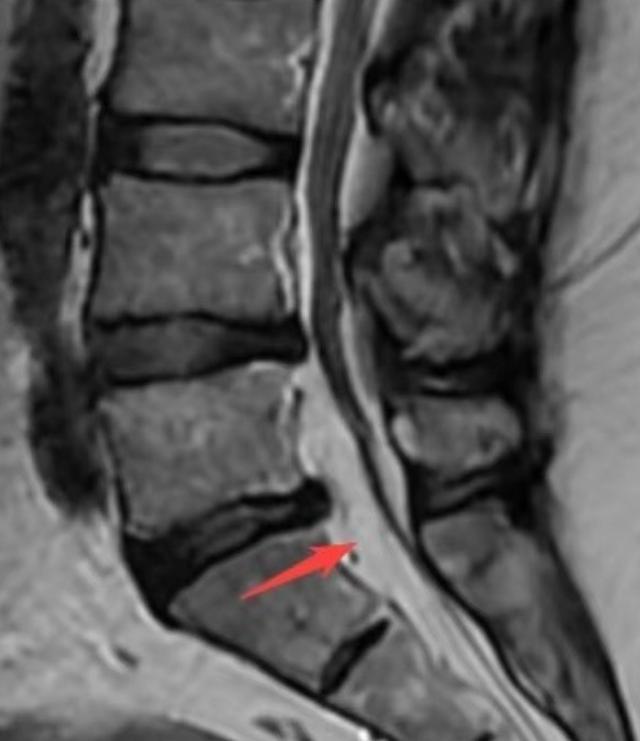

入院后的CT结果显示“椎间盘略有膨出”,这一结果难以解释他如此明显的不适症状。于是,在盛斌主任的建议下做了腰椎核磁共振,结果仍然显示:腰椎间盘轻微膨出,神经压迫不明显。为了找到导致患者症状如此严重的根源,盛斌主任反复仔细查阅影像资料后发现,其腰椎管内有异常增生的脂肪信号,初步判断为少见的“椎管内硬膜外脂肪增多症”。

▲术前MRI显示:椎管内有异常增多的脂肪信号

“该病发病率仅为2.5%~25%,好发于肥胖人群,男性更为多见。”盛斌主任解释,正常人的椎管内都含有少量的脂肪组织,如果脂肪含量异常增多,对脊髓和神经产生明显压迫,就会出现相应的神经压迫症状。当脂肪增多位于脊髓胸段水平时,最常见的症状为进行性背痛;当发生于脊髓腰骶段水平时,可出现髋部、下肢缓慢进行性无力,多发神经根病,麻木、感觉异常,间歇性跛行,大小便失禁,共济失调等症状。